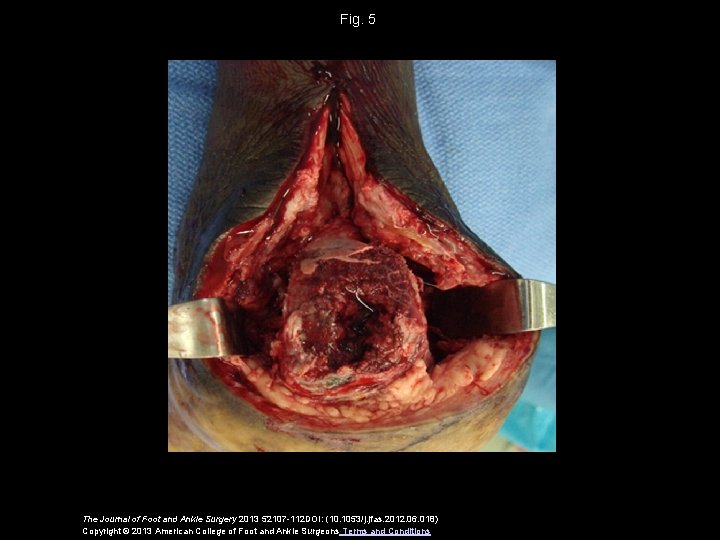

Fig. 5 The Journal of Foot and Ankle Surgery 2013 52107 -112 DOI: (10. 1053/j. jfas. 2012. 06. 018) Copyright © 2013 American College of Foot and Ankle Surgeons Terms and Conditions